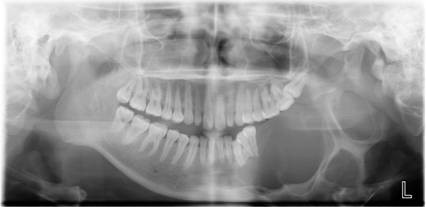

数字化口腔曲面体层片